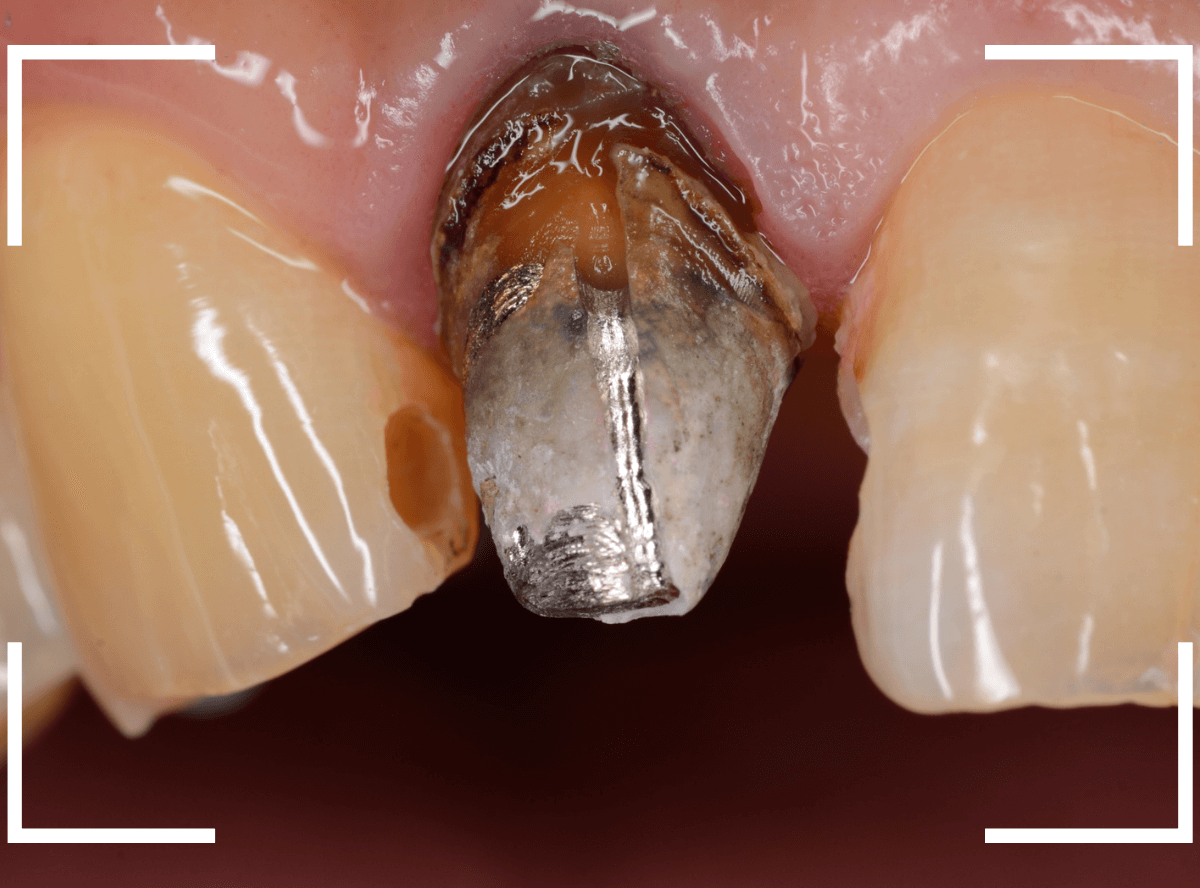

さし歯を外すと、金属の土台(メタル・コア)が出てきました。

慎重に土台を外して、中を調べます。

赤く染色されている部分が虫歯の残っているです。

慎重に虫歯を除去して、土台の型を取ります。

新たに、ファイバー・コアを製作し、setします。

今回は、オール・ジルコニアでの治療を希望されましたので、最終の型を取ります。